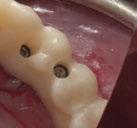

Exploración Intraoral

Presenta un estado oral deficitario. Parcialmente edéntula, con colapso de mordida, migración dental patológica, restauraciones de resina antiguas fisuradas y filtradas, transparencia y exposición de cámara pulpar secundaria a desgastes con pérdida de estructura e integridad de tejido dental importante (Figuras 1 a 4). Portadora a tiempo parcial de prótesis removibles desadaptadas de más de 10 años de antigüedad, refiriendo incapacidad de adaptación a este tipo de prótesis.

Figura 3. Visión intraoral oclusal mandibular. Figura 4. Visión intraoral frontal. Figura 1. Visión intraoral oclusal maxilar. Figura 2. Visión lateral izquierda intraoral. Figura 7. Escaneado intraoral maxilar con Dexis IS3700. Figura 8. Escaneado intraoral mandibular con Dexis IS3700. Figura 5. Visión extraoral lateral sonrisa.